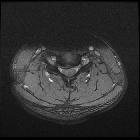

Disc protrusions are a type of disc herniation characterized by protrusion of disc content beyond the normal confines of the intervertebral disc, over a segment less than 25% of the circumference of the disc. The width of the base is wider than the largest diameter of the disc material which projects beyond the normal disc margins. The protrusion must not extend above or below the relevant vertebral endplates .

A disc protrusion is also described in terms of its axial position, into central, subarticular, foraminal, extraforaminal, or anterior locations .

Additionally, the terms contained (outer annulus fibrosus laminae are intact) and non-contained (all laminae are deficient) are also sometimes used .